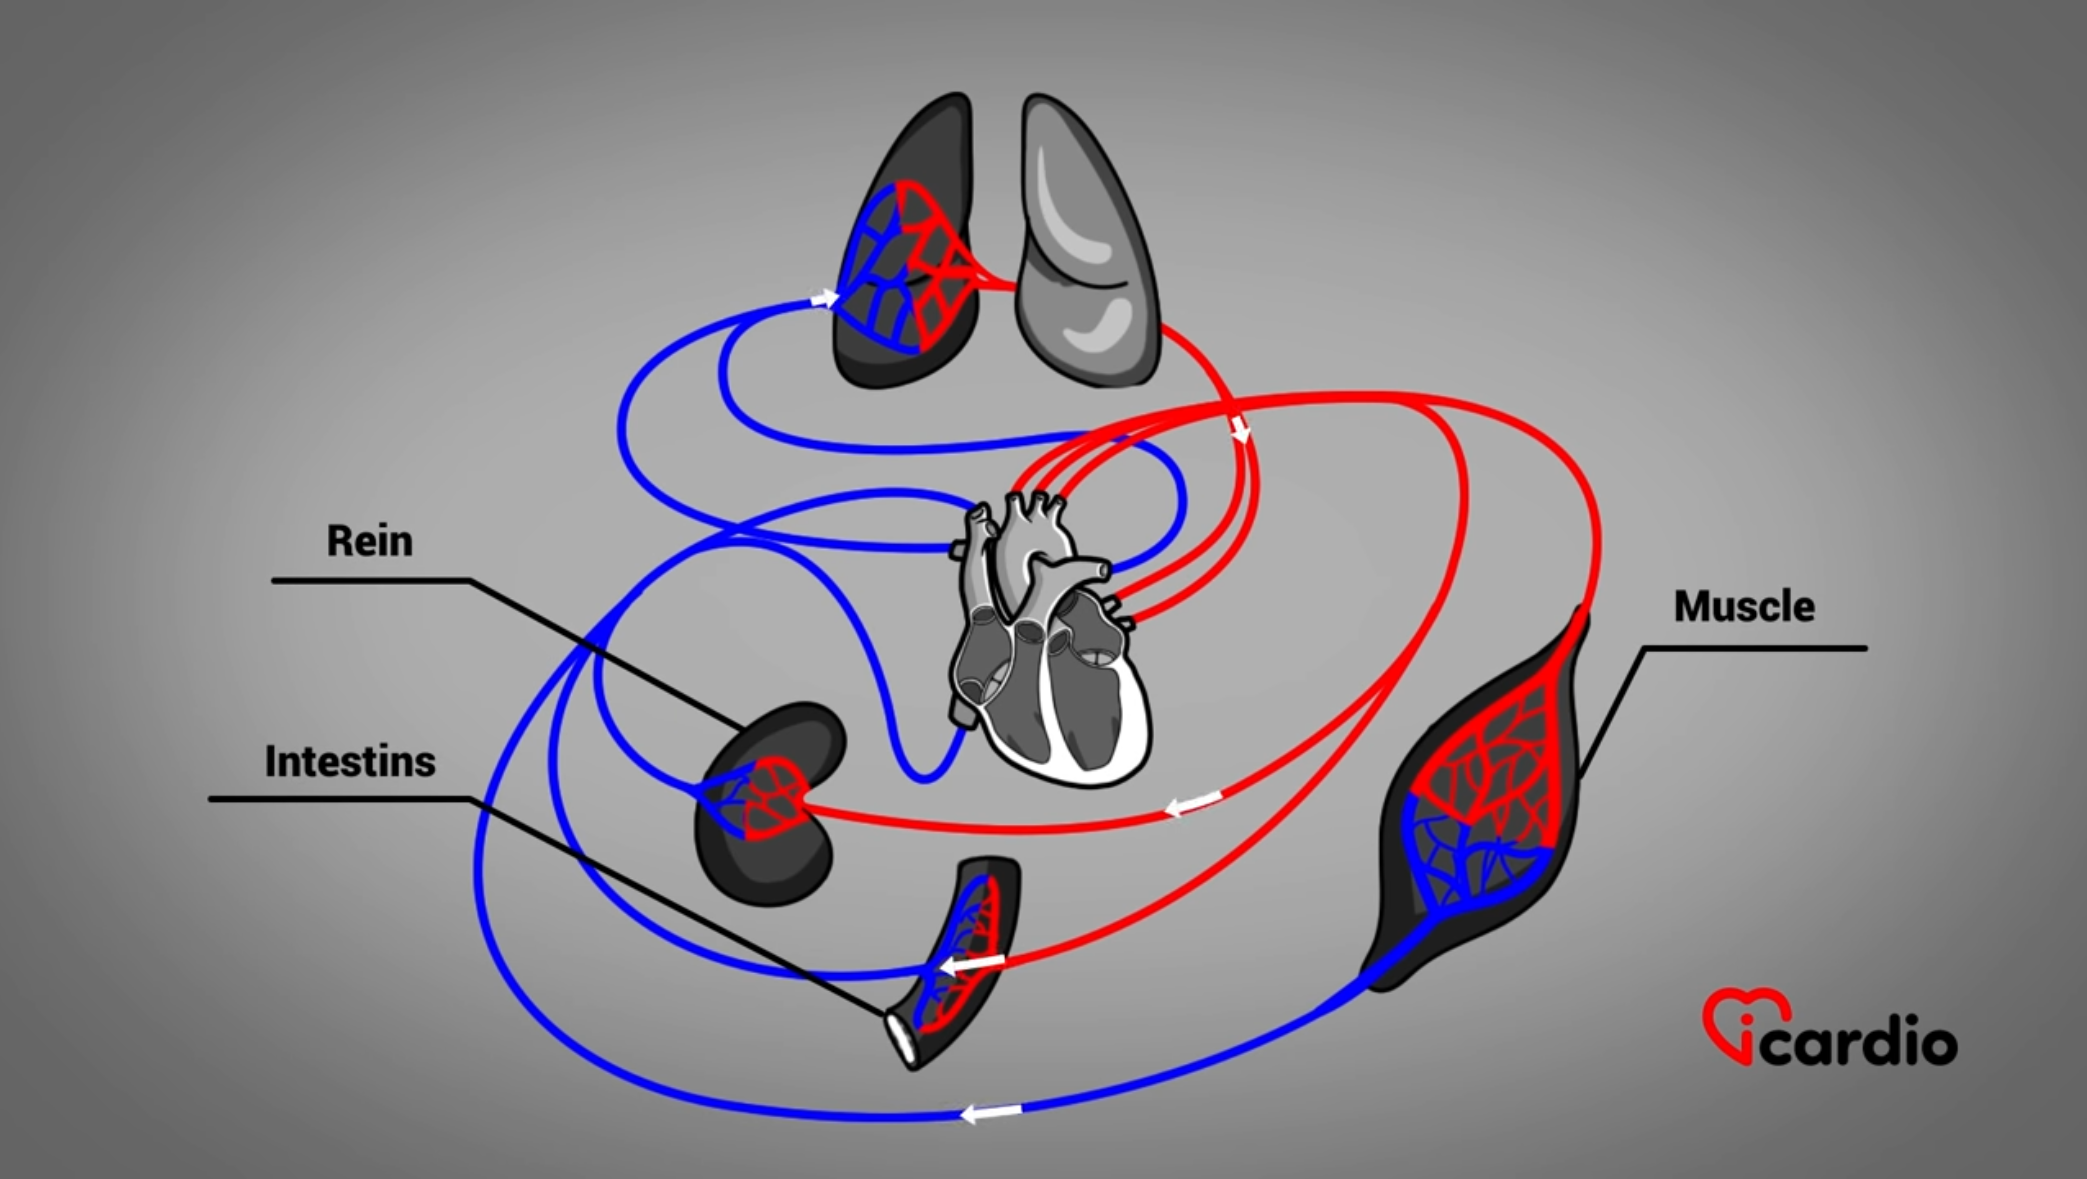

Le cœur est un organe musculaire situé au centre de la poitrine, entre les poumons. Il est de la grosseur d’un poing fermé.

C’est un organe merveilleux, presque infatigable. Il permet de faire circuler le sangLe sang est composé de globules rouges, de globules blancs, de plaquettes et de plasma. Les globules rouges sont responsables du transport de l’oxygène et du dioxyde de carbone. Les globules blancs constituent notre système de défense >> dans tout l’organisme.